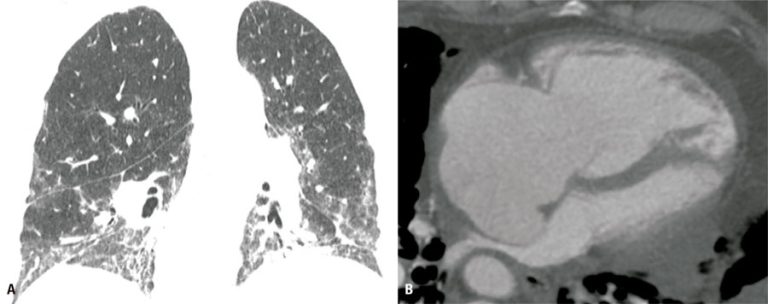

Computed tomography imaging features of major pulmonary and extrapulmonary complications of fibrotic lung diseases

DOI: 10.31744/einstein_journal/2026RW0987

ABSTRACT Patients diagnosed with fibrosing interstitial lung disease are at risk of several complications, some of which may be life-threatening. Computed tomography imaging plays an important role in diagnosing these overlapping conditions. This article summarizes the computed tomography imaging features of the most common conditions associated with fibrosing interstitial lung diseases, categorized by involvement of the lung parenchyma or extra-pulmonary compartments. Some steps may help to recognize such complications, such as having knowledge of the underlying fibrotic lung disease, being […]